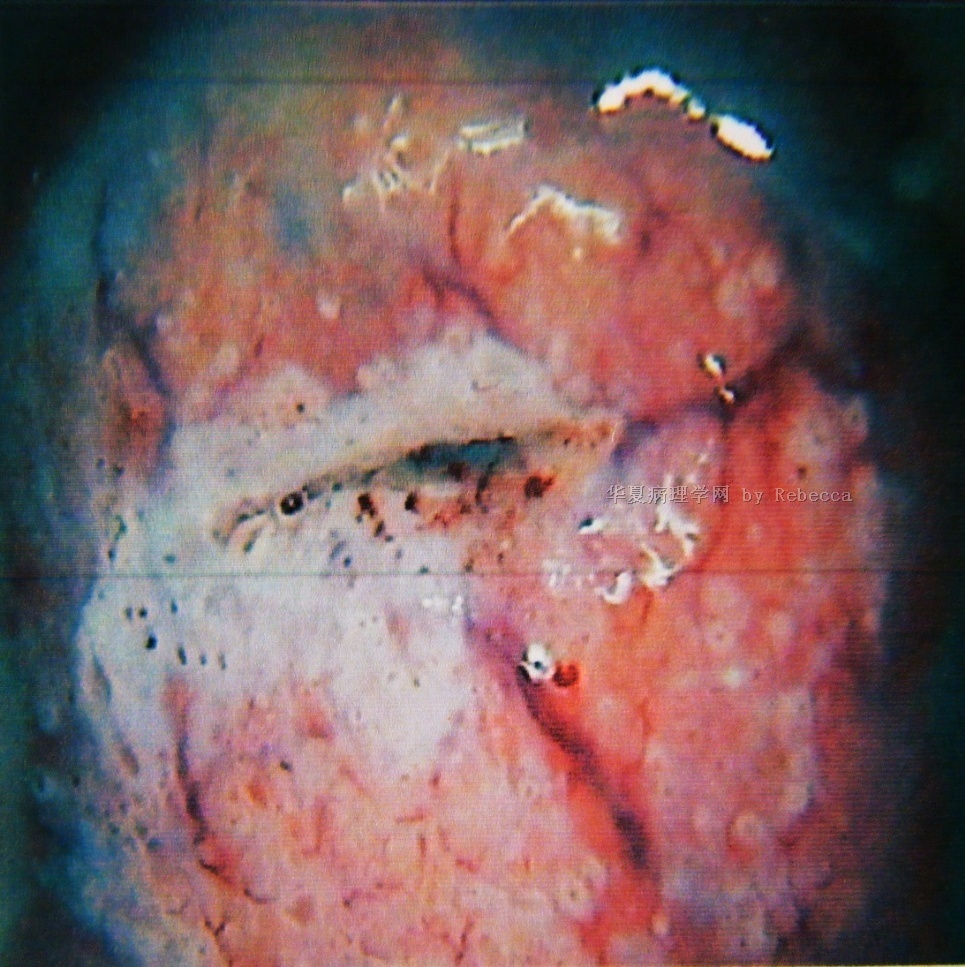

宫颈癌

图中醋白上皮边缘卷曲,浓厚,稍隆起于宫颈,可见粗点状血管,大部分

宫颈口长菜花状赘生物